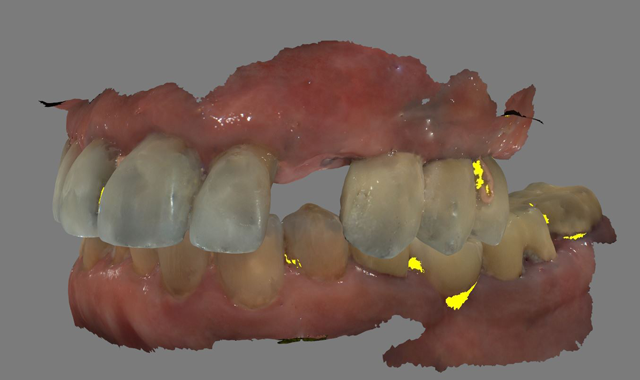

A 61-year-old male presented to my office with a fractured maxillary left canine. His past medical history was significant for previous DVT for which he was taking Coumadin. He has no known allergies (Fig. 1).

Fig. 1 Fig. 2

A CBCT scan was taken with a Carestream Dental CS 9300 (Figs. 2 and 3) and an intraoral scan was obtained using a Carestream Dental intraoral scanner (Figs. 4 and 5).